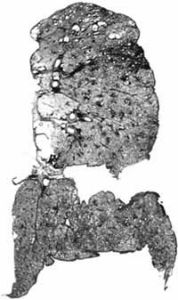

煤工塵肺2.X線檢查煤工塵肺胸片表現特徵有:網狀改變;結節狀改變;結節融合;塊狀陰影和多量絨毛狀改變。網狀改變被認為是煤工塵肺最早的表現,在肺野呈現瀰漫性細網狀陰影。而此時在臨床上無任何症狀。隨著結節的擴展,病變融合成不透明的進行性大塊纖維化,通常位於兩肺上野,也可跨肺葉融合至中、下肺野,有時僅發生在一側肺野,通常為大塊狀,均勻的、界限明顯的陰影。這些改變往往在單純性煤工塵肺彌散結節陰影的背景上發生。

伴有類風濕性關節炎的煤工塵肺患者,即Caplan綜合徵的胸部X線片往往呈現多個圓形、邊界清晰、分布較均勻的結節。在雙肺甚至分布至肺野周圍部分。圓形結節直徑可從0.5~5cm,但通常為1cm左右。有時病變出現與關節炎並無明顯相關性,或開始出現關節炎後病情迅速發展。在Caplan肺部病變可出現中心空洞,鈣化以及病變融合現象。在進行性大塊纖維化患者或有重度吸菸史者多合併有肺氣腫,嚴重肺氣腫往往致使肺部點狀和小結節顯示不清,易導致臨床醫生對病變